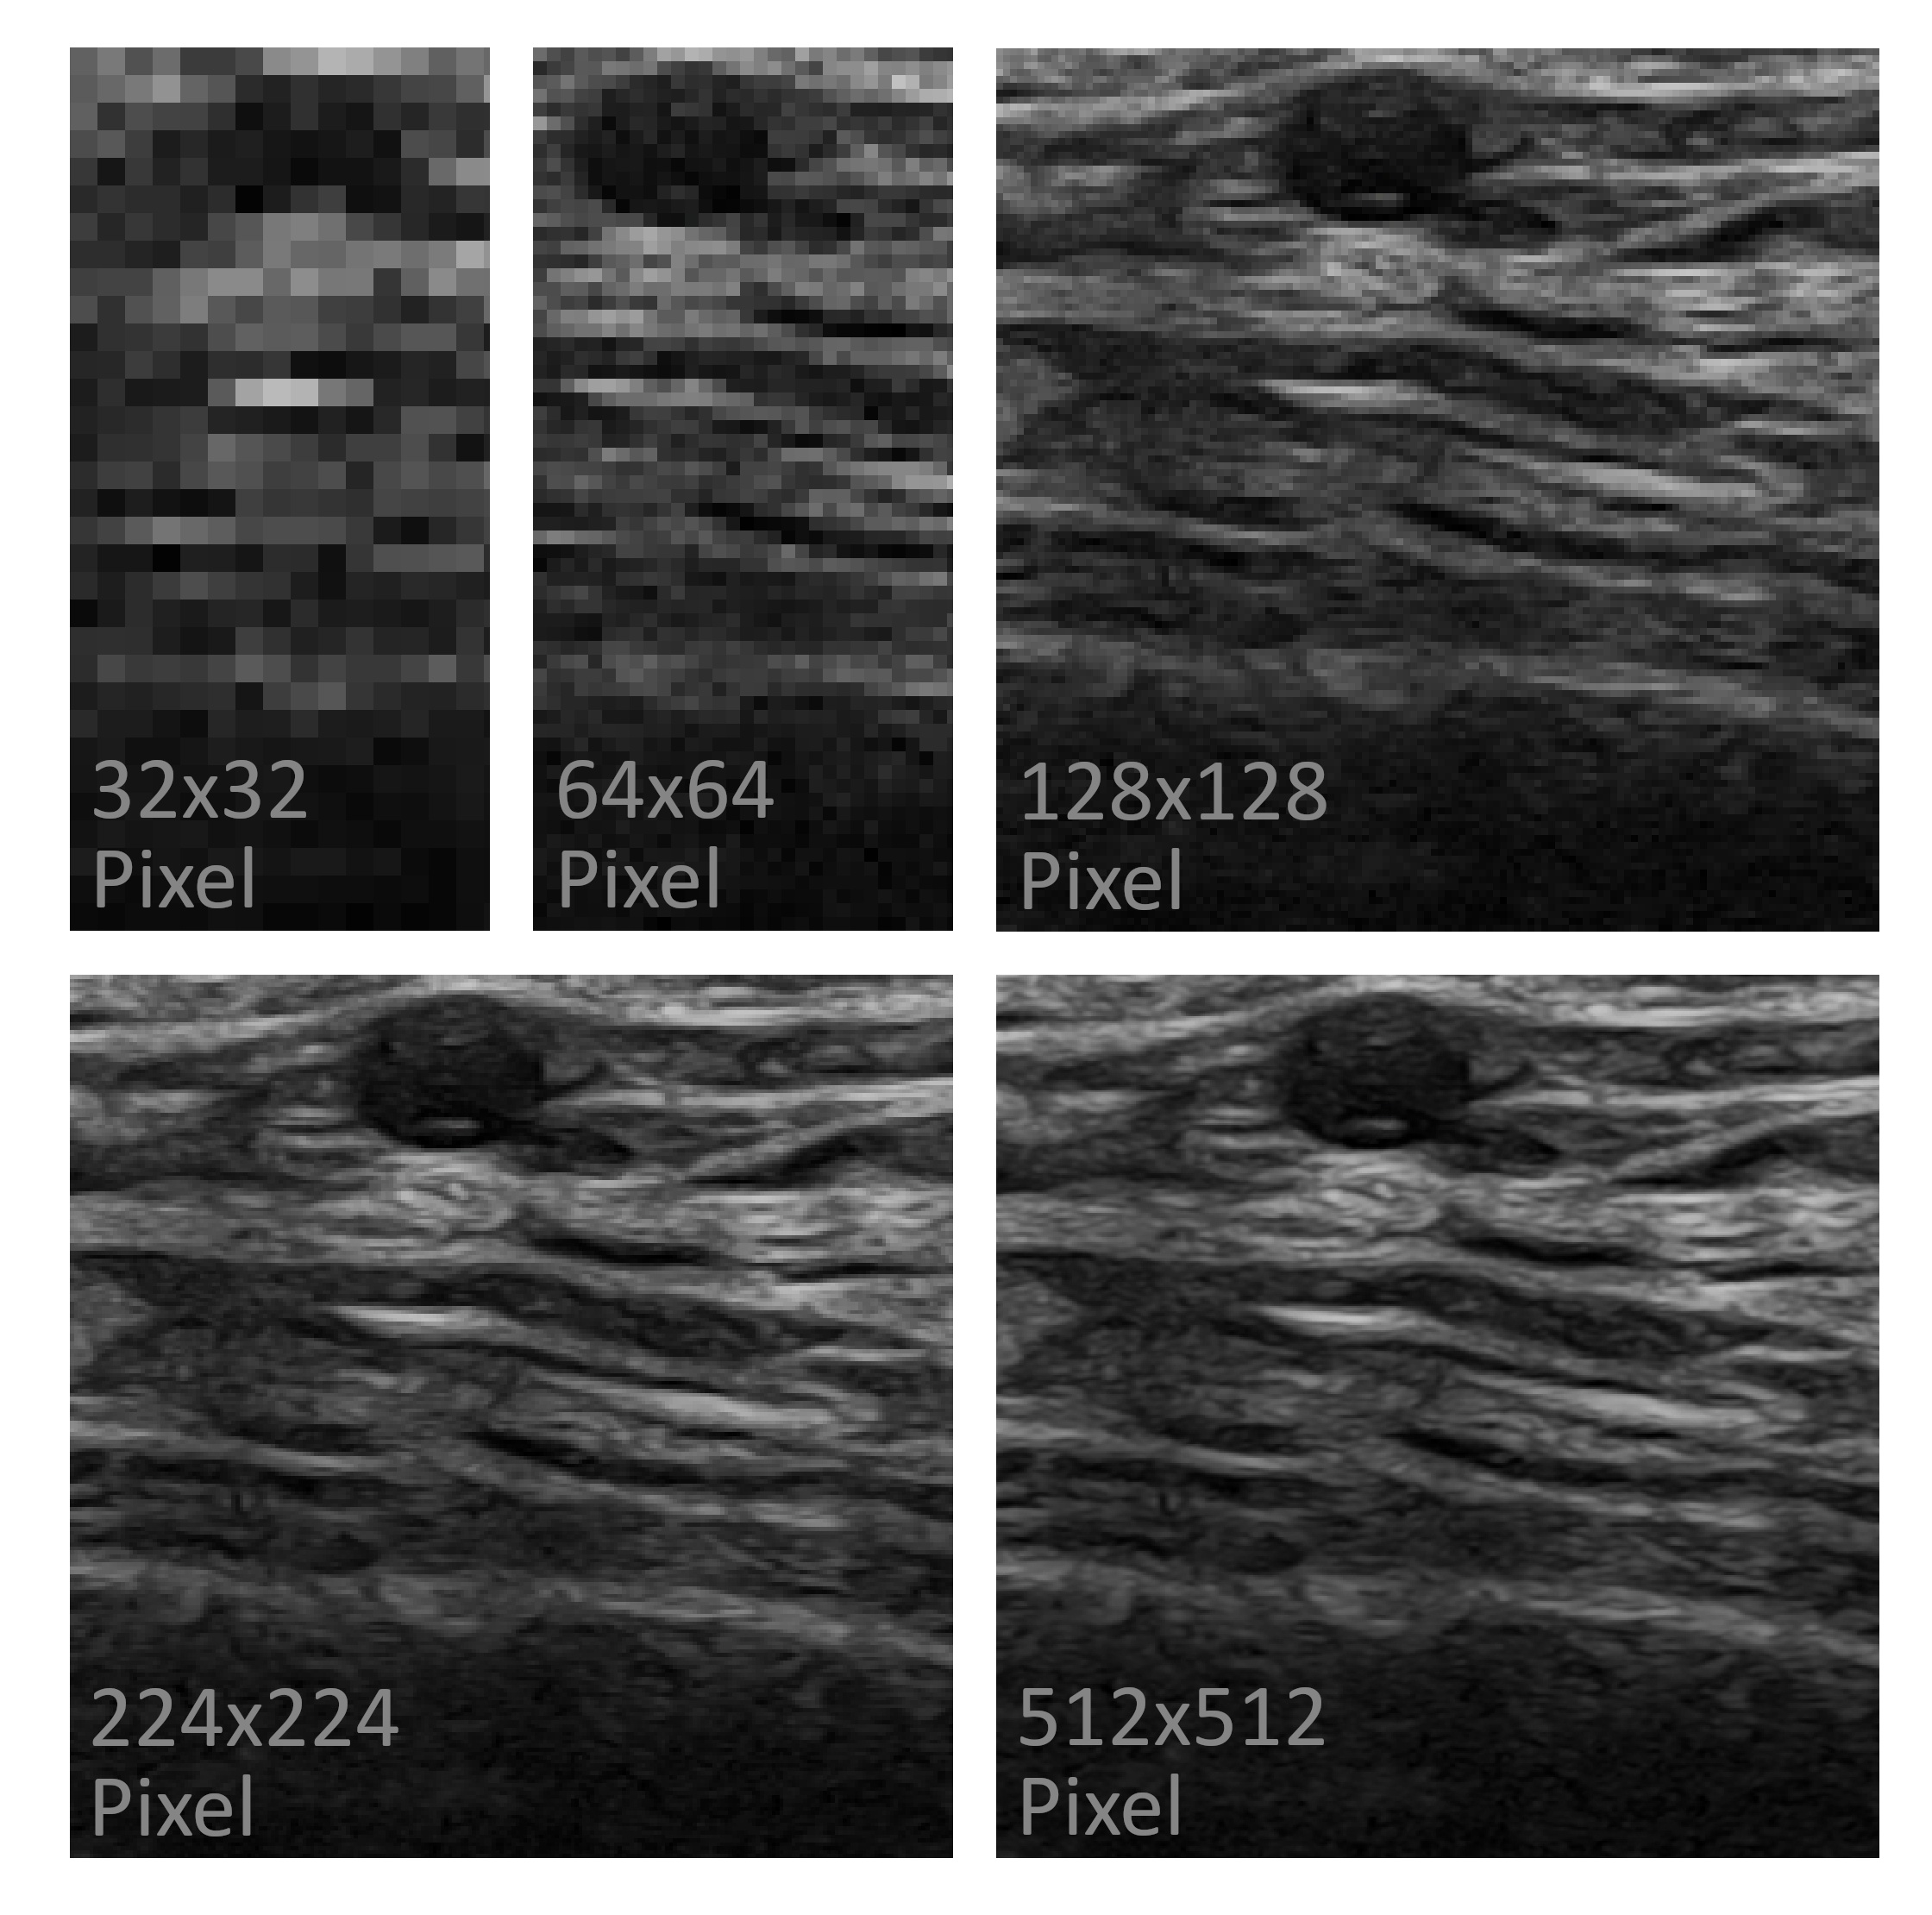

Methods: In this study, a blinded classification task was conducted, involving 42 international experts from the OMERACT subgroup on ultrasound in large vessel vasculitis. A set of 250 vascular ultrasound images from both GCA patients and healthy individuals were presented to the experts. The image selection process initially comprised 10 B-mode scans each of the common temporal artery, its frontal branch, parietal branch, and the axillary artery (all in cross-section), as well as the axillary artery in longitudinal scan. These 50 images were presented in a random order at five distinct resolution levels: 32x32, 64x64, 128x128, 224x224, and 512x512 pixels (refer to Figure 1). The survey and image classification tasks were conducted using REDCap version 13.2.5, while data interim analysis was performed utilizing R (version 4.3.0).

Figure 1: Shown is an exemplary ultrasound image of the common temporal artery (cross-section, B-mode), presented to study participants at five different resolution levels.